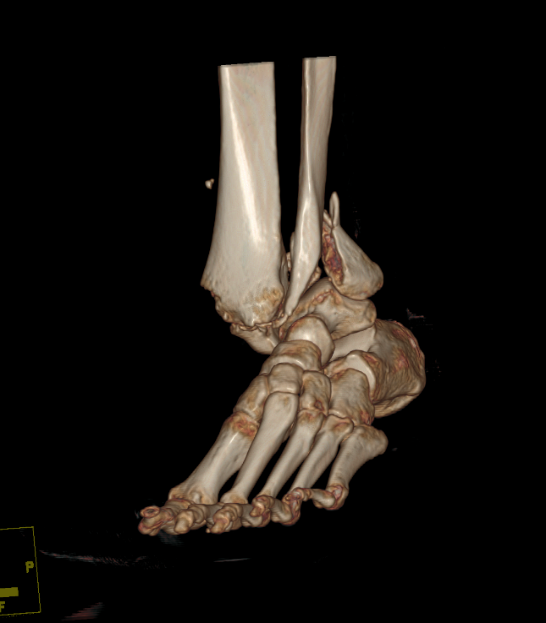

病例五:患者,女,56岁,因“车祸伤致左踝关节肿痛伴活动受限14小时”入院。诊断:左侧三踝粉碎性骨折伴踝关节脱位;行左踝关节骨折切开复位内固定术;手术顺利,术后进行康复训练中,功能恢复良好。

左侧三踝粉碎性骨折 术前三维CT

左侧三踝粉碎性骨折 术后X线片